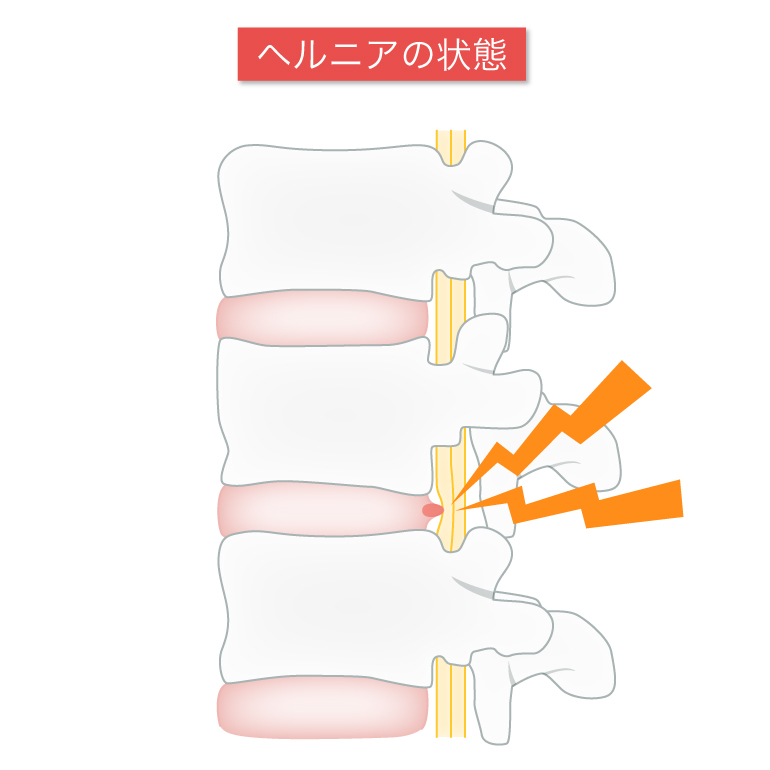

腰椎椎間板ヘルニアはどんな病気ですか?

椎間板内の組織の一部が飛び出して神経を圧迫する病気です。

「腰椎椎間板ヘルニア」は、腰の痛みや足の痛み、しびれといった症状が出ます。症状が腰の痛みだけしか出ないこともあります(10%程度)。

重症化すると、足のまひや排尿・排便の障害を生じることがあります。

腰椎椎間板ヘルニアの主な原因は、椎間板にかかる強い圧力です。主には前屈みの姿勢で、急に重いものを持ったり、中腰や下を向く作業が多いと椎間板ヘルニアになりやすいと言われています。

弾力性のある椎間板を持つ若年層は、中腰で重いものを持ったときなど突発的に椎間板が飛び出してしまうことがあり、その場合激痛が走ります。